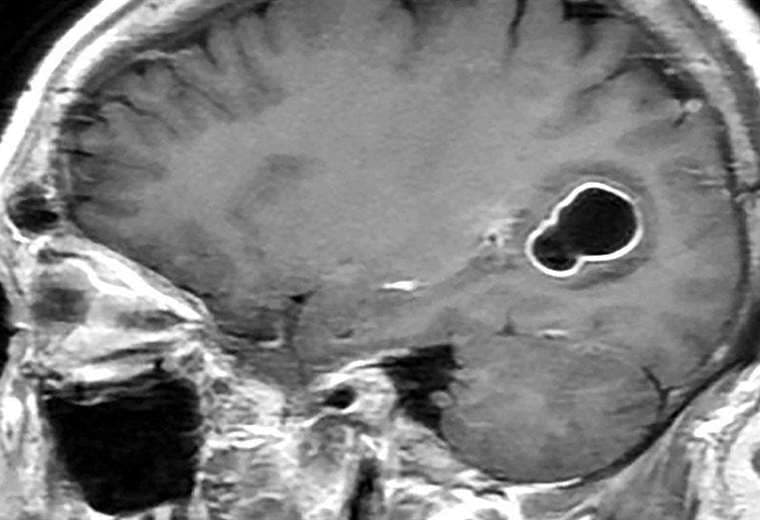

Al realizarle tomografías, los médicos encontraron la presencia de numerosos quistes en el cerebro que, según luego comprobaron con estudios posteriores, en realidad eran larvas de tenia que se habían instalado en su cerebro y que eran las causantes de una infección conocida como neurocisticercosis.

Esta infección es causada por las larvas del parásito Taenia solium (T.solium), también conocido como tenia del cerdo.

Según los Centros para el Control y la Prevención de Enfermedades (CDC, por sus siglas en inglés) de EE.UU., las larvas de tenia "entran en tejidos como los músculos y el cerebro y forman quistes. Cuando se encuentran quistes en el cerebro, la afección se llama neurocisticercosis".